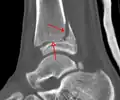

-

A triplane fracture of the ankle as seen on CT